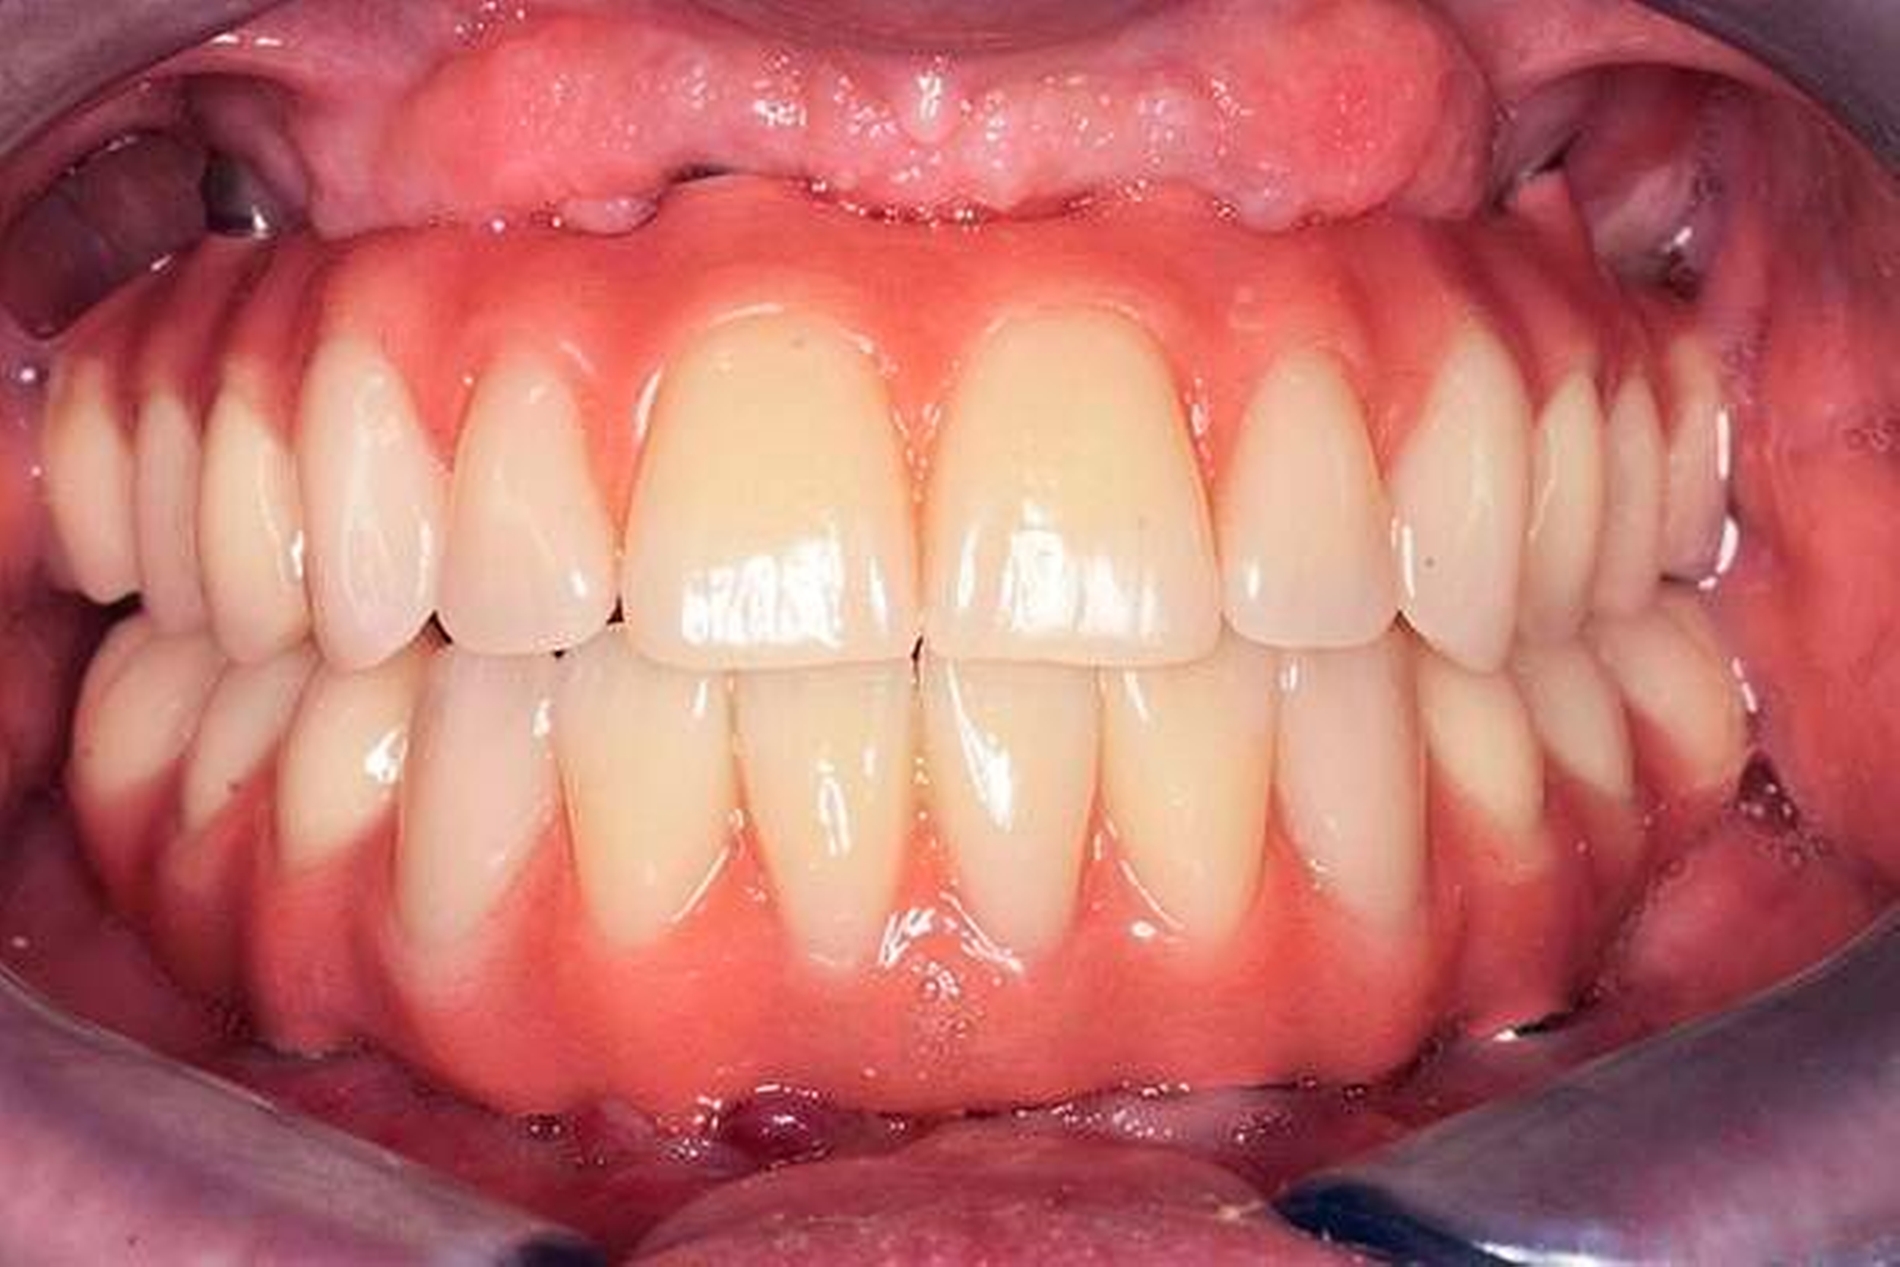

2. Phase: Gemäß unserem Protokoll wird nach frühestens sechs Monaten eine definitive Versorgung hergestellt, die mit einem im CAD/CAM-Verfahren hergestellten Titangerüst verstärkt ist und durch beidseitige Freienden typischerweise zwölf Zähne ersetzt. Hier gibt es die Möglichkeit zur Herstellung einer Brücke mit aufgestellten Kunststoffzähnen (Abbildung 3) oder individuell hergestellten, keramischen Einzelkronen (Abbildung 4).